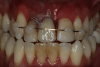

Fig 36. Anterior central view.

Figure 36